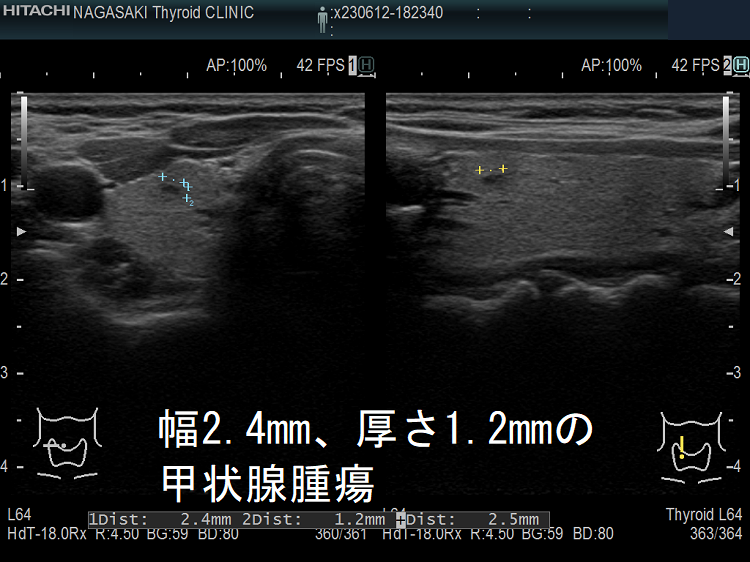

ケース② 幅2.4mm、厚さ1.2mmの甲状腺腫瘍

幅2.4mm、厚さ1.2mmの甲状腺腫瘍 超音波(エコー)画像

幅2.4mm、厚さ1.2mmの甲状腺腫瘍 超音波(エコー)画像;B-モードでは甲状腺のう胞(甲状腺嚢胞)甲状腺腫瘍か判別できません。

幅2.4mm、厚さ1.2mmの甲状腺腫瘍 ドプラーモード

幅2.4mm、厚さ1.2mmの甲状腺腫 超音波(エコー)画像 ドプラーモード;通常倍率でもドプラーモード[eFlow(イー フロー)]で内部微細血流を確認できるため、甲状腺腫瘍なのが判ります。